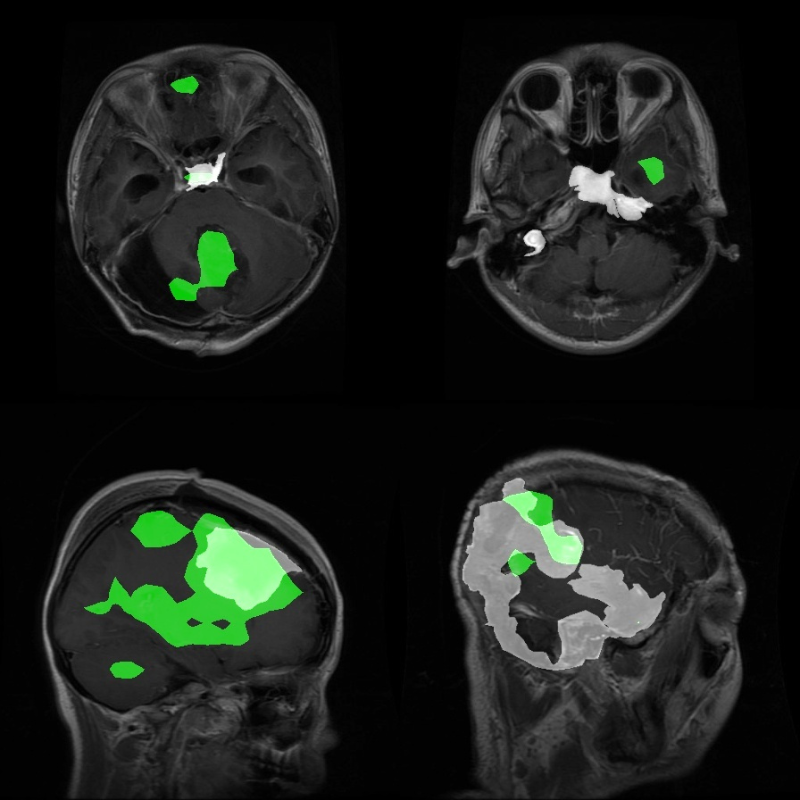

Now, some instances where the model fails.

Clearly, these results are not good.

Takeaways

The above experiment shows some glaring limitations of the model and the approach that we are following. We have used a simple, single-layer pixel classifier for the segmentation head. There is a chance that using a more complex, multi-layer feature aggregator will improve the results.

Furthermore, we can also pretrain such a pixel classifier on COCO segmentation datasets to make it learn complex features. Then we can use it for such complex experiments.